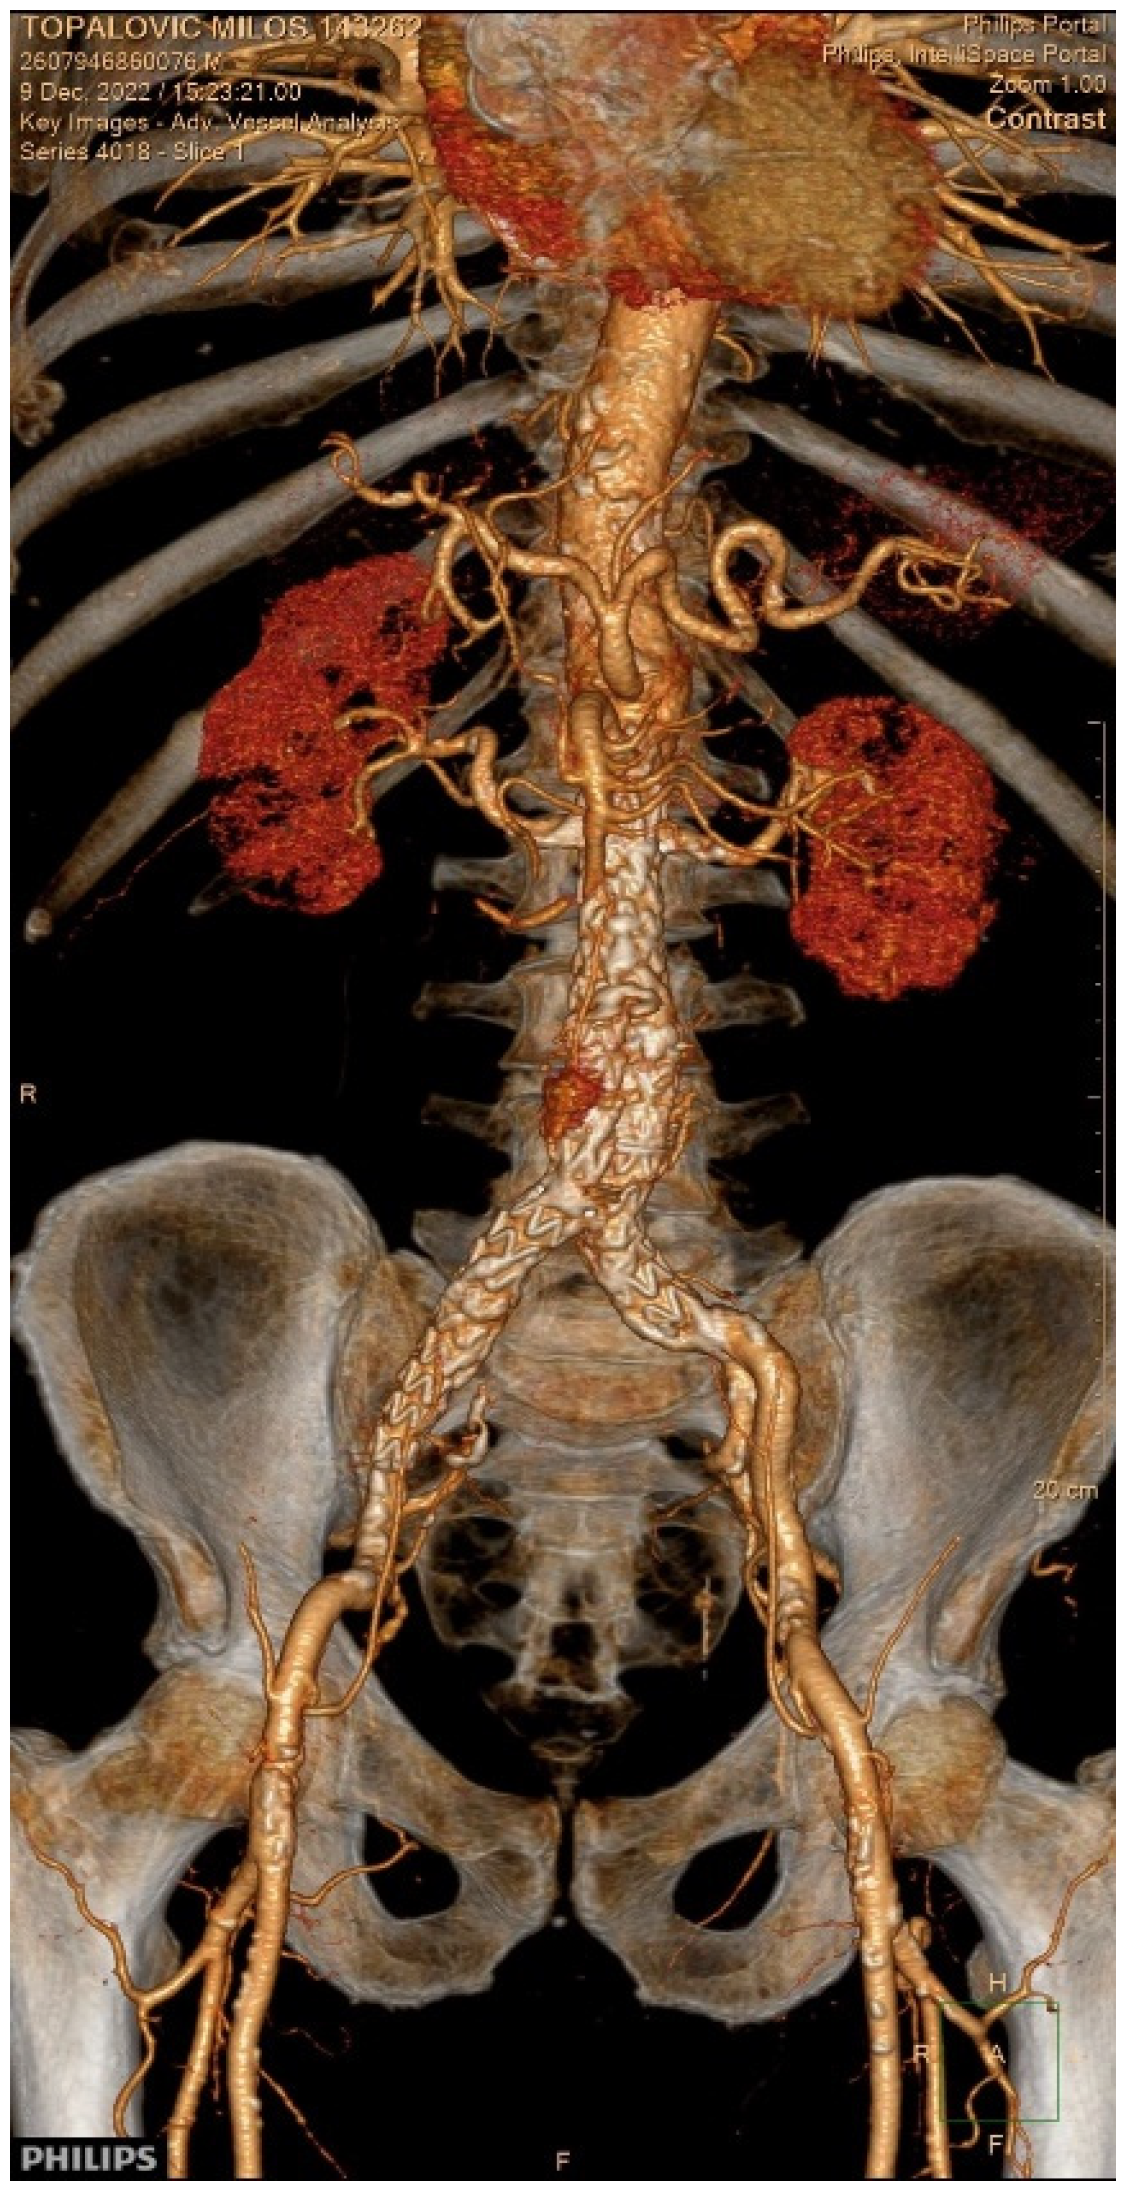

2. Case Presentation

3.8. Our Case